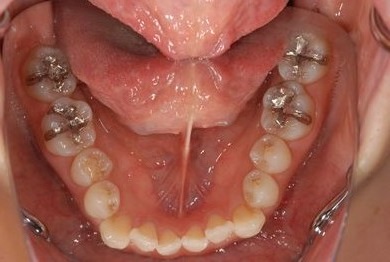

| 性別/年齢 | 女性 / 34歳 | ||||||||||||||||||||||||||||||||

| 主訴 | 以前虫歯を治療して金属を入れたところが、再び虫歯になったのか、軽くしみたり違和感がある。 | ||||||||||||||||||||||||||||||||

| 治療方針 | セラミック治療にて、審美的回復を行う。 | ||||||||||||||||||||||||||||||||

| 治療内容 | メタルボンドセラミッククラウン1本(メタルボンド用土台1本) | ||||||||||||||||||||||||||||||||

| 総治療費 | 125,685円 | ||||||||||||||||||||||||||||||||

| 治療期間 | 3ヶ月 |